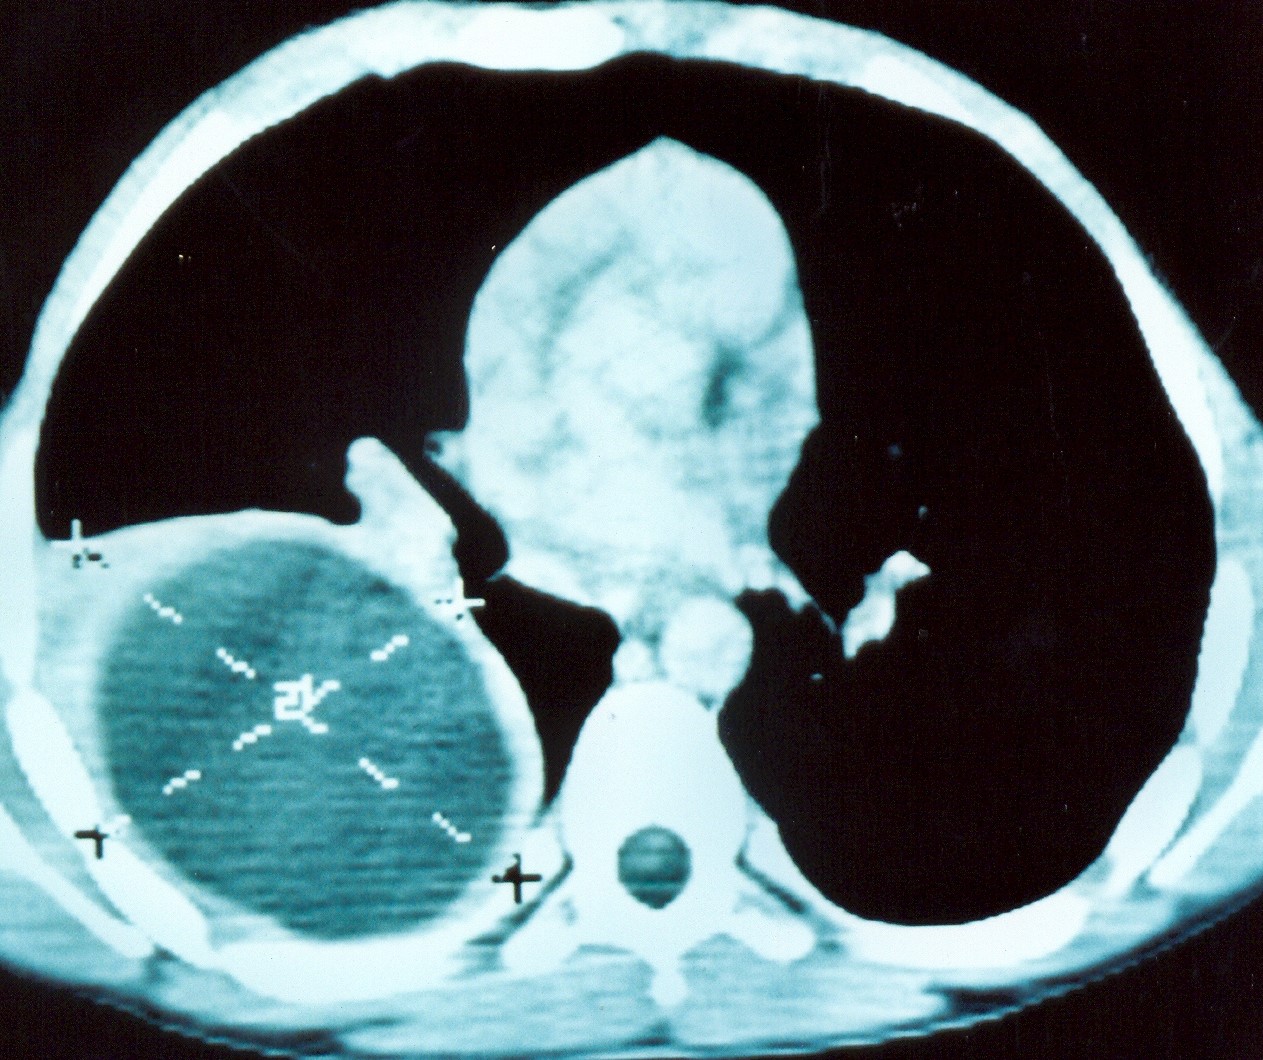

Upper abdominal CT scan 1 year after splenic autotransplantation. Enhancement of the transplanted splenic tissue after contrast injection is evident, demonstrating its viability and function (Courtesy Dr. V. Penopoulos)